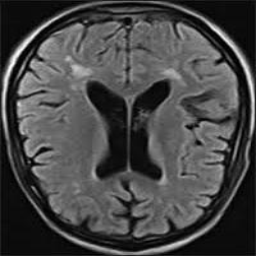

• Brain Tumor MRI Dataset (BMRI) [33]: The three datasets below are combined to create this dataset: figshare, SARTAJ, Br35H. There are 7023 MRI images of the human brain in this collection, divided into 4 categories: pituitary, glioma, meningioma, and no tumor. Images categorized as the ’no tumor’ class were obtained from the Br35H dataset.

• Chest X-ray Dataset (CXR) [34]: This dataset originates from the NIH, which is the largest chest radiograph data set. From 30,805 special patients, 112,120 frontal X-ray images are collected. Each X-ray is linked to the associated text disease label, which is drawn from the relevant radiological reports using an NLP algorithm.

• Lung Cancer CT Dataset (LCT) [35]: From different specialist hospitals, the IQ-OTH/NCCD lung cancer dataset was collected over three months in the fall of 2019. It comprises CT scans from patients with lung cancer in different stages and healthy subjects, totaling 1190 images from 110 cases. The dataset, marked by oncologists and radiologists, categorizes cases into three classes: normal (55 cases), benign (15 cases), and malignant (40 cases).

The proposed QMedShield’s security is evaluated using a number of metrics and proved that it is resistant to various cryptographic attacks including brute-force attacks, statistical attacks, histogram attacks, and differential attacks. Throughout the section, 6 sample medical images BMRI1,BMRI2,CXR1,CXR2,LCT1,LCT2𝐵𝑀𝑅subscript𝐼1𝐵𝑀𝑅subscript𝐼2𝐶𝑋subscript𝑅1𝐶𝑋subscript𝑅2𝐿𝐶subscript𝑇1𝐿𝐶subscript𝑇2BMRI_{1},BMRI_{2},CXR_{1},CXR_{2},LCT_{1},LCT_{2} are taken (2 images from each dataset) to show the performance comparison. The selection of MRI, X-ray, and CT images for the encryption task aims to demonstrate the versatility and effectiveness of our model across various imaging modalities, showcasing its applicability and robustness in diverse clinical scenarios. Figure 11 shows the selected sample medical images and their corresponding encrypted images.

Refer to caption

(a) BMRI1𝐵𝑀𝑅subscript𝐼1BMRI_{1}

(b) CXR1𝐶𝑋subscript𝑅1CXR_{1}

(c) LCT1𝐿𝐶subscript𝑇1LCT_{1}

(d) BMRI2𝐵𝑀𝑅subscript𝐼2BMRI_{2}

(e) CXR2𝐶𝑋subscript𝑅2CXR_{2}

(f) LCT2𝐿𝐶subscript𝑇2LCT_{2}

(g) E(BMRI1)𝐸𝐵𝑀𝑅subscript𝐼1E(BMRI_{1})

(h) E(CXR1)𝐸𝐶𝑋subscript𝑅1E(CXR_{1})

(i) E(LCT1)𝐸𝐿𝐶subscript𝑇1E(LCT_{1})

(j) E(BMRI2)𝐸𝐵𝑀𝑅subscript𝐼2E(BMRI_{2})

(k) E(CXR2)𝐸𝐶𝑋subscript𝑅2E(CXR_{2})

(l) E(LCT2)𝐸𝐿𝐶subscript𝑇2E(LCT_{2})

Figure 11: Selected sample plain medical images and the corresponding encrypted cipher images